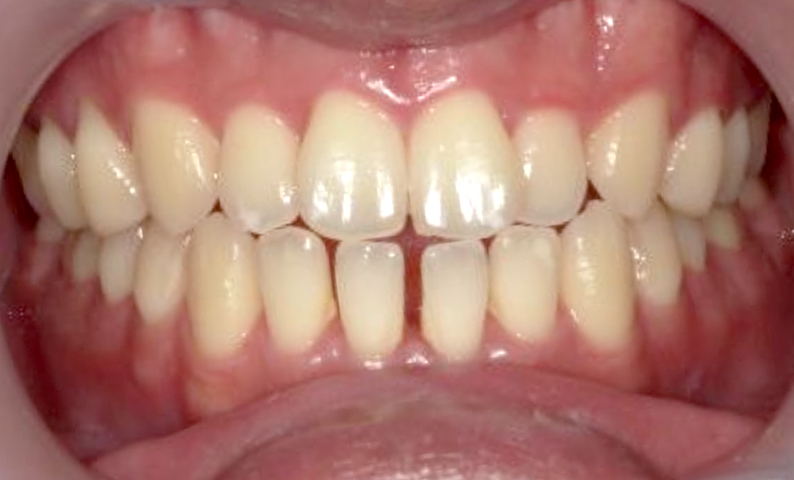

| 治療前 | 治療後 |

|---|---|

|